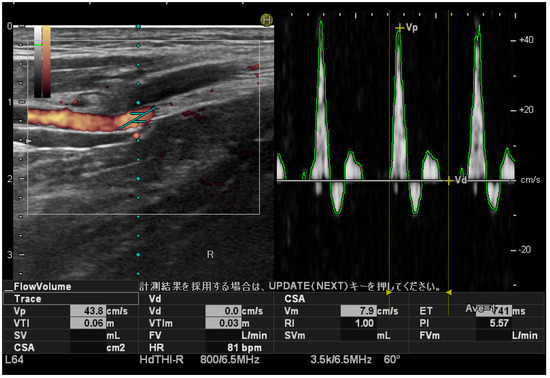

The PTA blood flow velocity was measured with the participant in a supine position on the bed, and the inside and outside malleolus of the foot juxtaposed approximately 5 cm from the edge of the bed. During imaging, the PTA was identified using the power Doppler method in the short-axis image at a position where the medial malleolus was visible in the B-mode. The peak systolic velocity (PSV) of the PTA was measured using the pulse Doppler method at a slant angle of 20° and an incidence angle of 60° in the blood flow direction relative to the direction of the ultrasound beam (Figure 1). The PSV was measured three times, and the average value was calculated. Measurements were performed bilaterally.

Figure 1.

Peak systolic velocity measurement of the posterior tibial artery. Ultrasound images. Pulse Doppler sonograms of the posterior tibial artery confirmed that the blood flow had a three-phase waveform. The slant angle is adjusted manually.